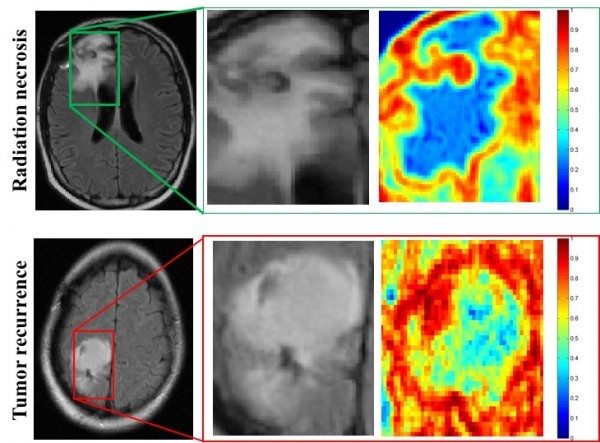

Escaneos por resonancia magnética de pacientes con necrosis por radiación (arriba) y con reaparición del cáncer (abajo), mostrados en la columna izquierda. Los primeros planos en la columna central muestran que las regiones de interés son esencialmente indistinguibles entre un escaneo y el otro, ambos rutinarios. Un análisis más profundo pone de manifiesto diferencias que muestran que la necrosis por radiación, en el recuadro derecho superior, tiene más homogeneidad, vista en azul, en comparación con la reincidencia del cáncer, abajo a la derecha, que tiene un grado notable de heterogeneidad, visible en rojo. (Imágenes: Pallavi Tiwari)

Para desarrollar el programa, el equipo de Pallavi Tiwari, de la Universidad Case Western Reserve, empleó algoritmos de aprendizaje automático para análisis de rasgos presentes en imágenes obtenidas por resonancia magnética. Médicos, científicos e ingenieros adiestraron al sistema informático para que pudiera identificar por su cuenta rasgos, sutiles aunque delatadores, con los que es posible distinguir entre el cáncer cerebral y la necrosis por radiación. Como material de análisis emplearon escaneos de resonancia magnética rutinarios de seguimiento de 43 pacientes.

El equipo desarrolló después algoritmos para encontrar los rasgos más fiables con los que diferenciar entre ambas situaciones, concretamente texturas que no pueden ser captadas por un ser humano que mire a ojo desnudo las imágenes.